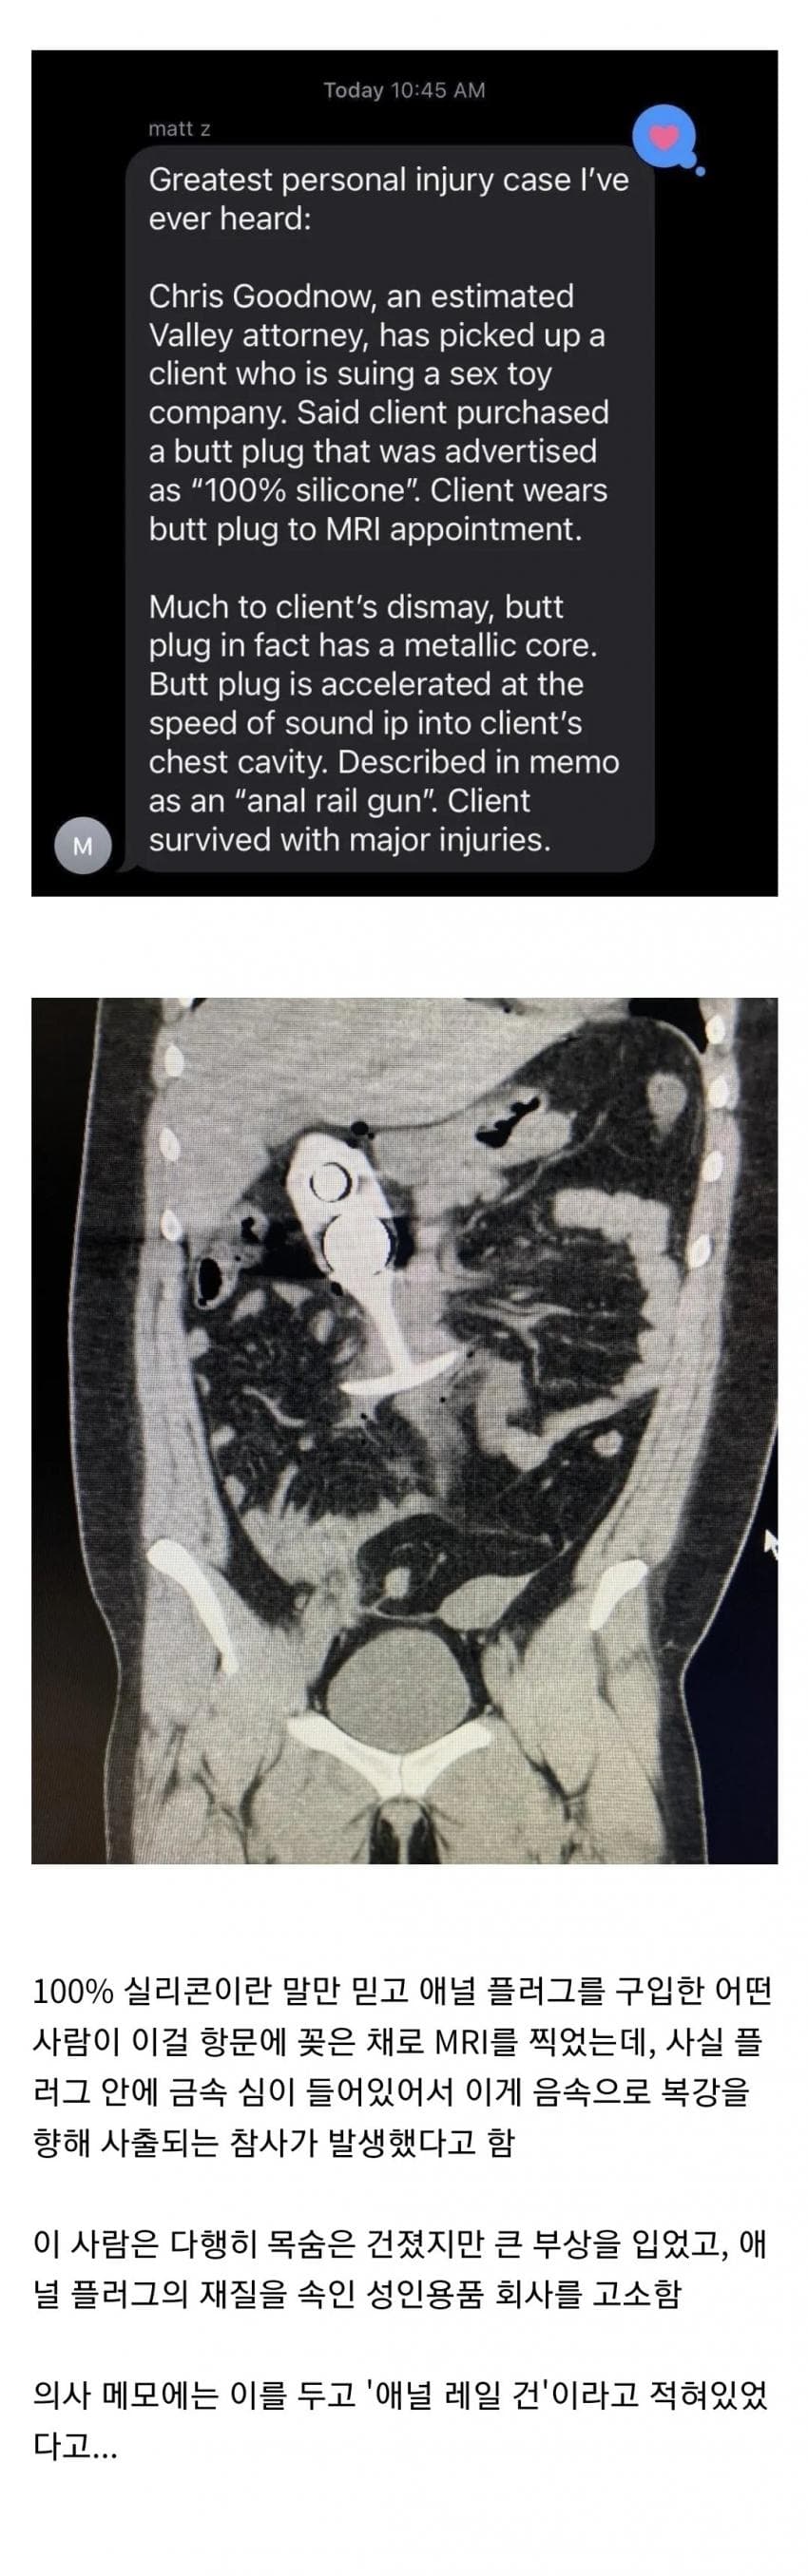

흔치않은 레일건 사고 작성자 정보 Apro 작성 작성일 2024.07.07 15:27 컨텐츠 정보 4,004 조회 목록 상품명흔치않은 레일건 사고 여행기간 출발지 교통편 상품가격성인  원 /  아동  원